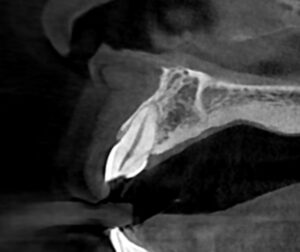

破折は神経の部屋(歯髄)までは達していなかったですが、亀裂がだいぶ深く骨まで及んでいました。

分かりますでしょうか。亀裂が口蓋側の歯槽骨まで達しています。こうなってしまうと、骨の中で処置はできませんので抜歯となる可能性が高くなります。しかし、歯を保存する方法も考えられます。